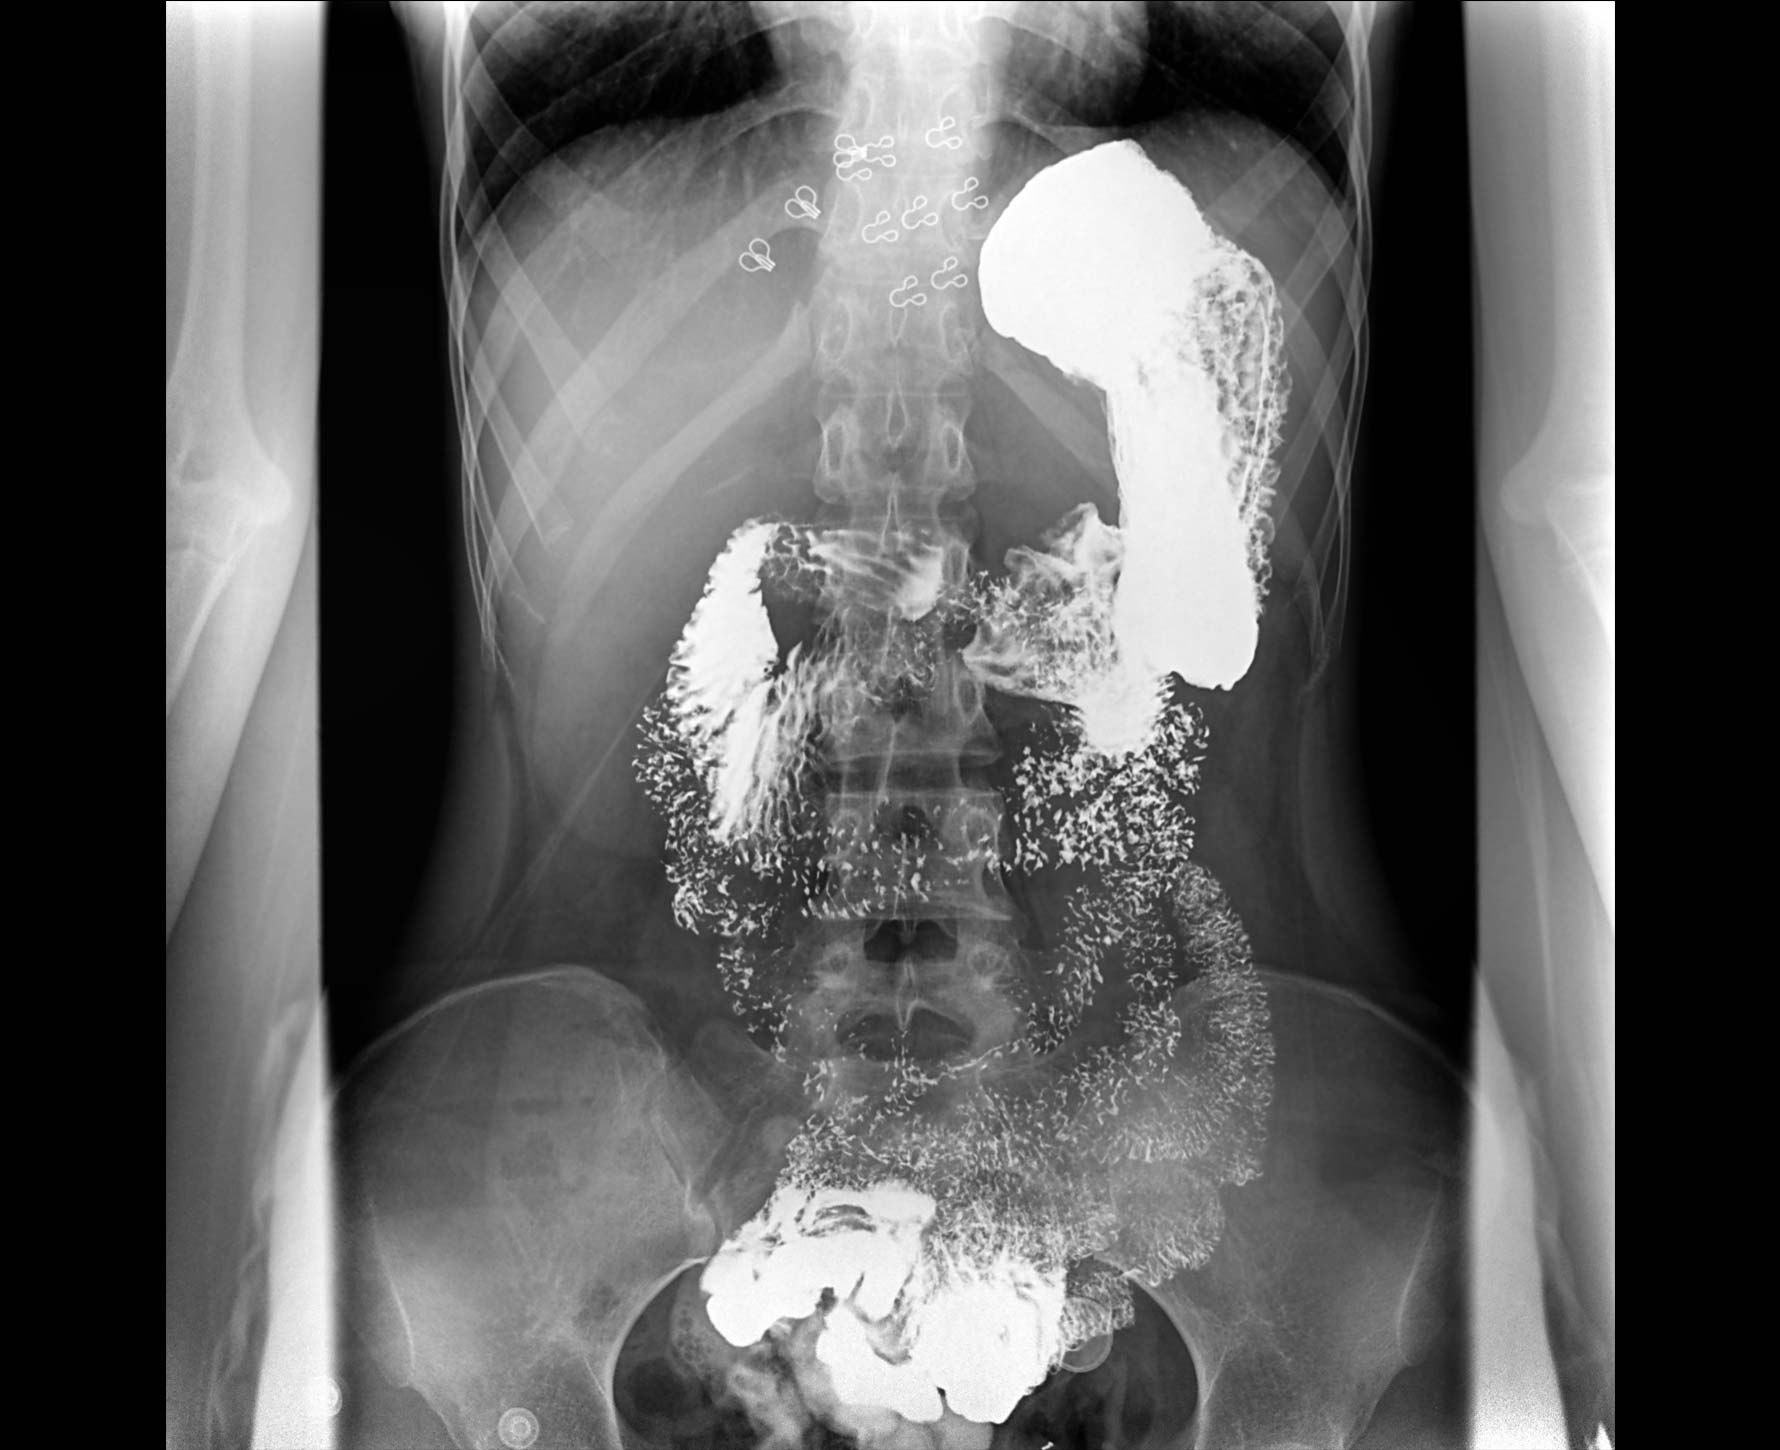

• 造影

适用于各种普通

及特殊胃肠造影检查